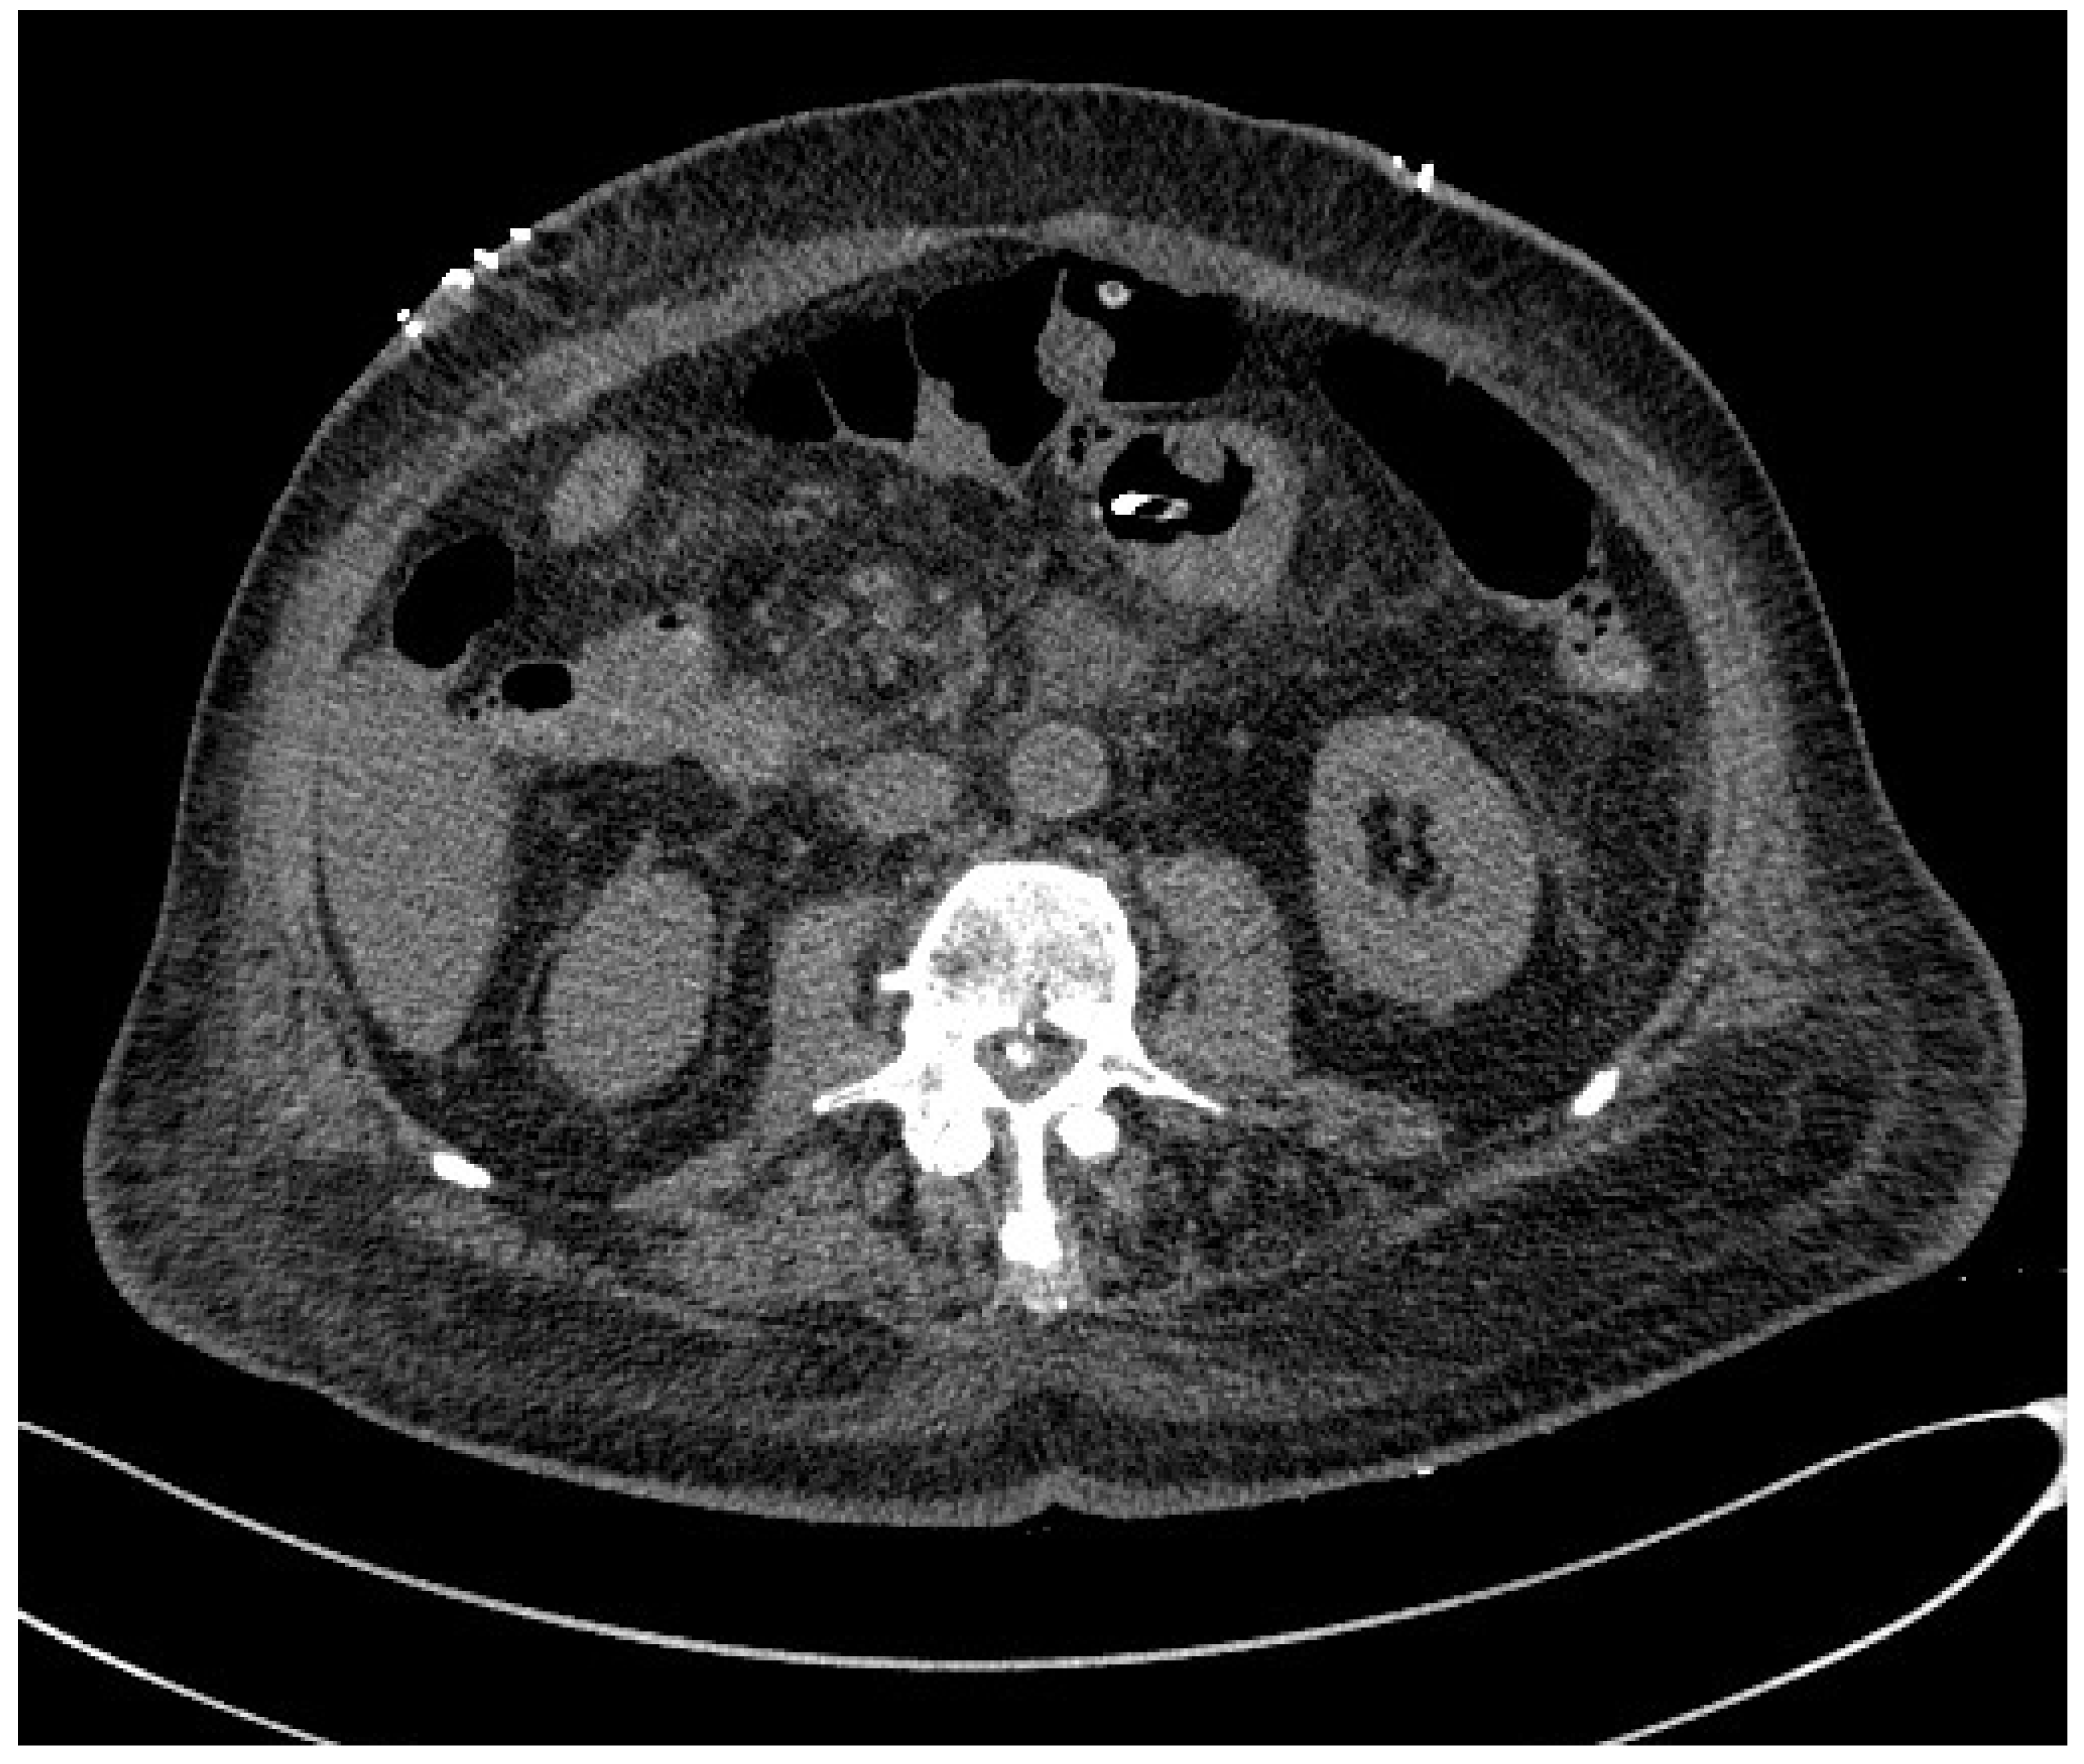

3.1. Computed Tomography